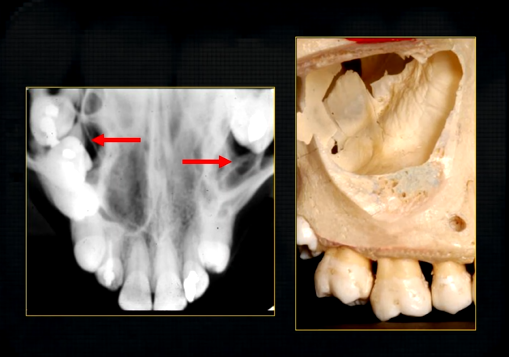

posteriorly, the maxilla….

widens as it articulates with the zygoma or cheekbone

The zygomatic buttress is a key vertical support structure of the midface, formed by the junction of the zygomatic process of the maxilla and the zygomatic bone

underneath the surface layer of the maxilla

large cavity - maxillary air sinuses /antrum -can extend anteriorly almost to the midline or posteriorly, to hollow out the zygoma

maxillary sinus is evident radiographically when the upper posterior teeth are shown

internally, the maxillary sinus is not smooth ….

there are small ridges and bumps- thin in cross sections - can appear as dense white opaque lines radiographically

bulk/prominence of the zygomatic cheekbone - radiographically this can overly the apical tissues of the upper molar teeth - solid, dense, white shadow

if its hollowed out by the maxillary sinus, it casts a white, radiopaque U shaped shadow - radiolucent centre